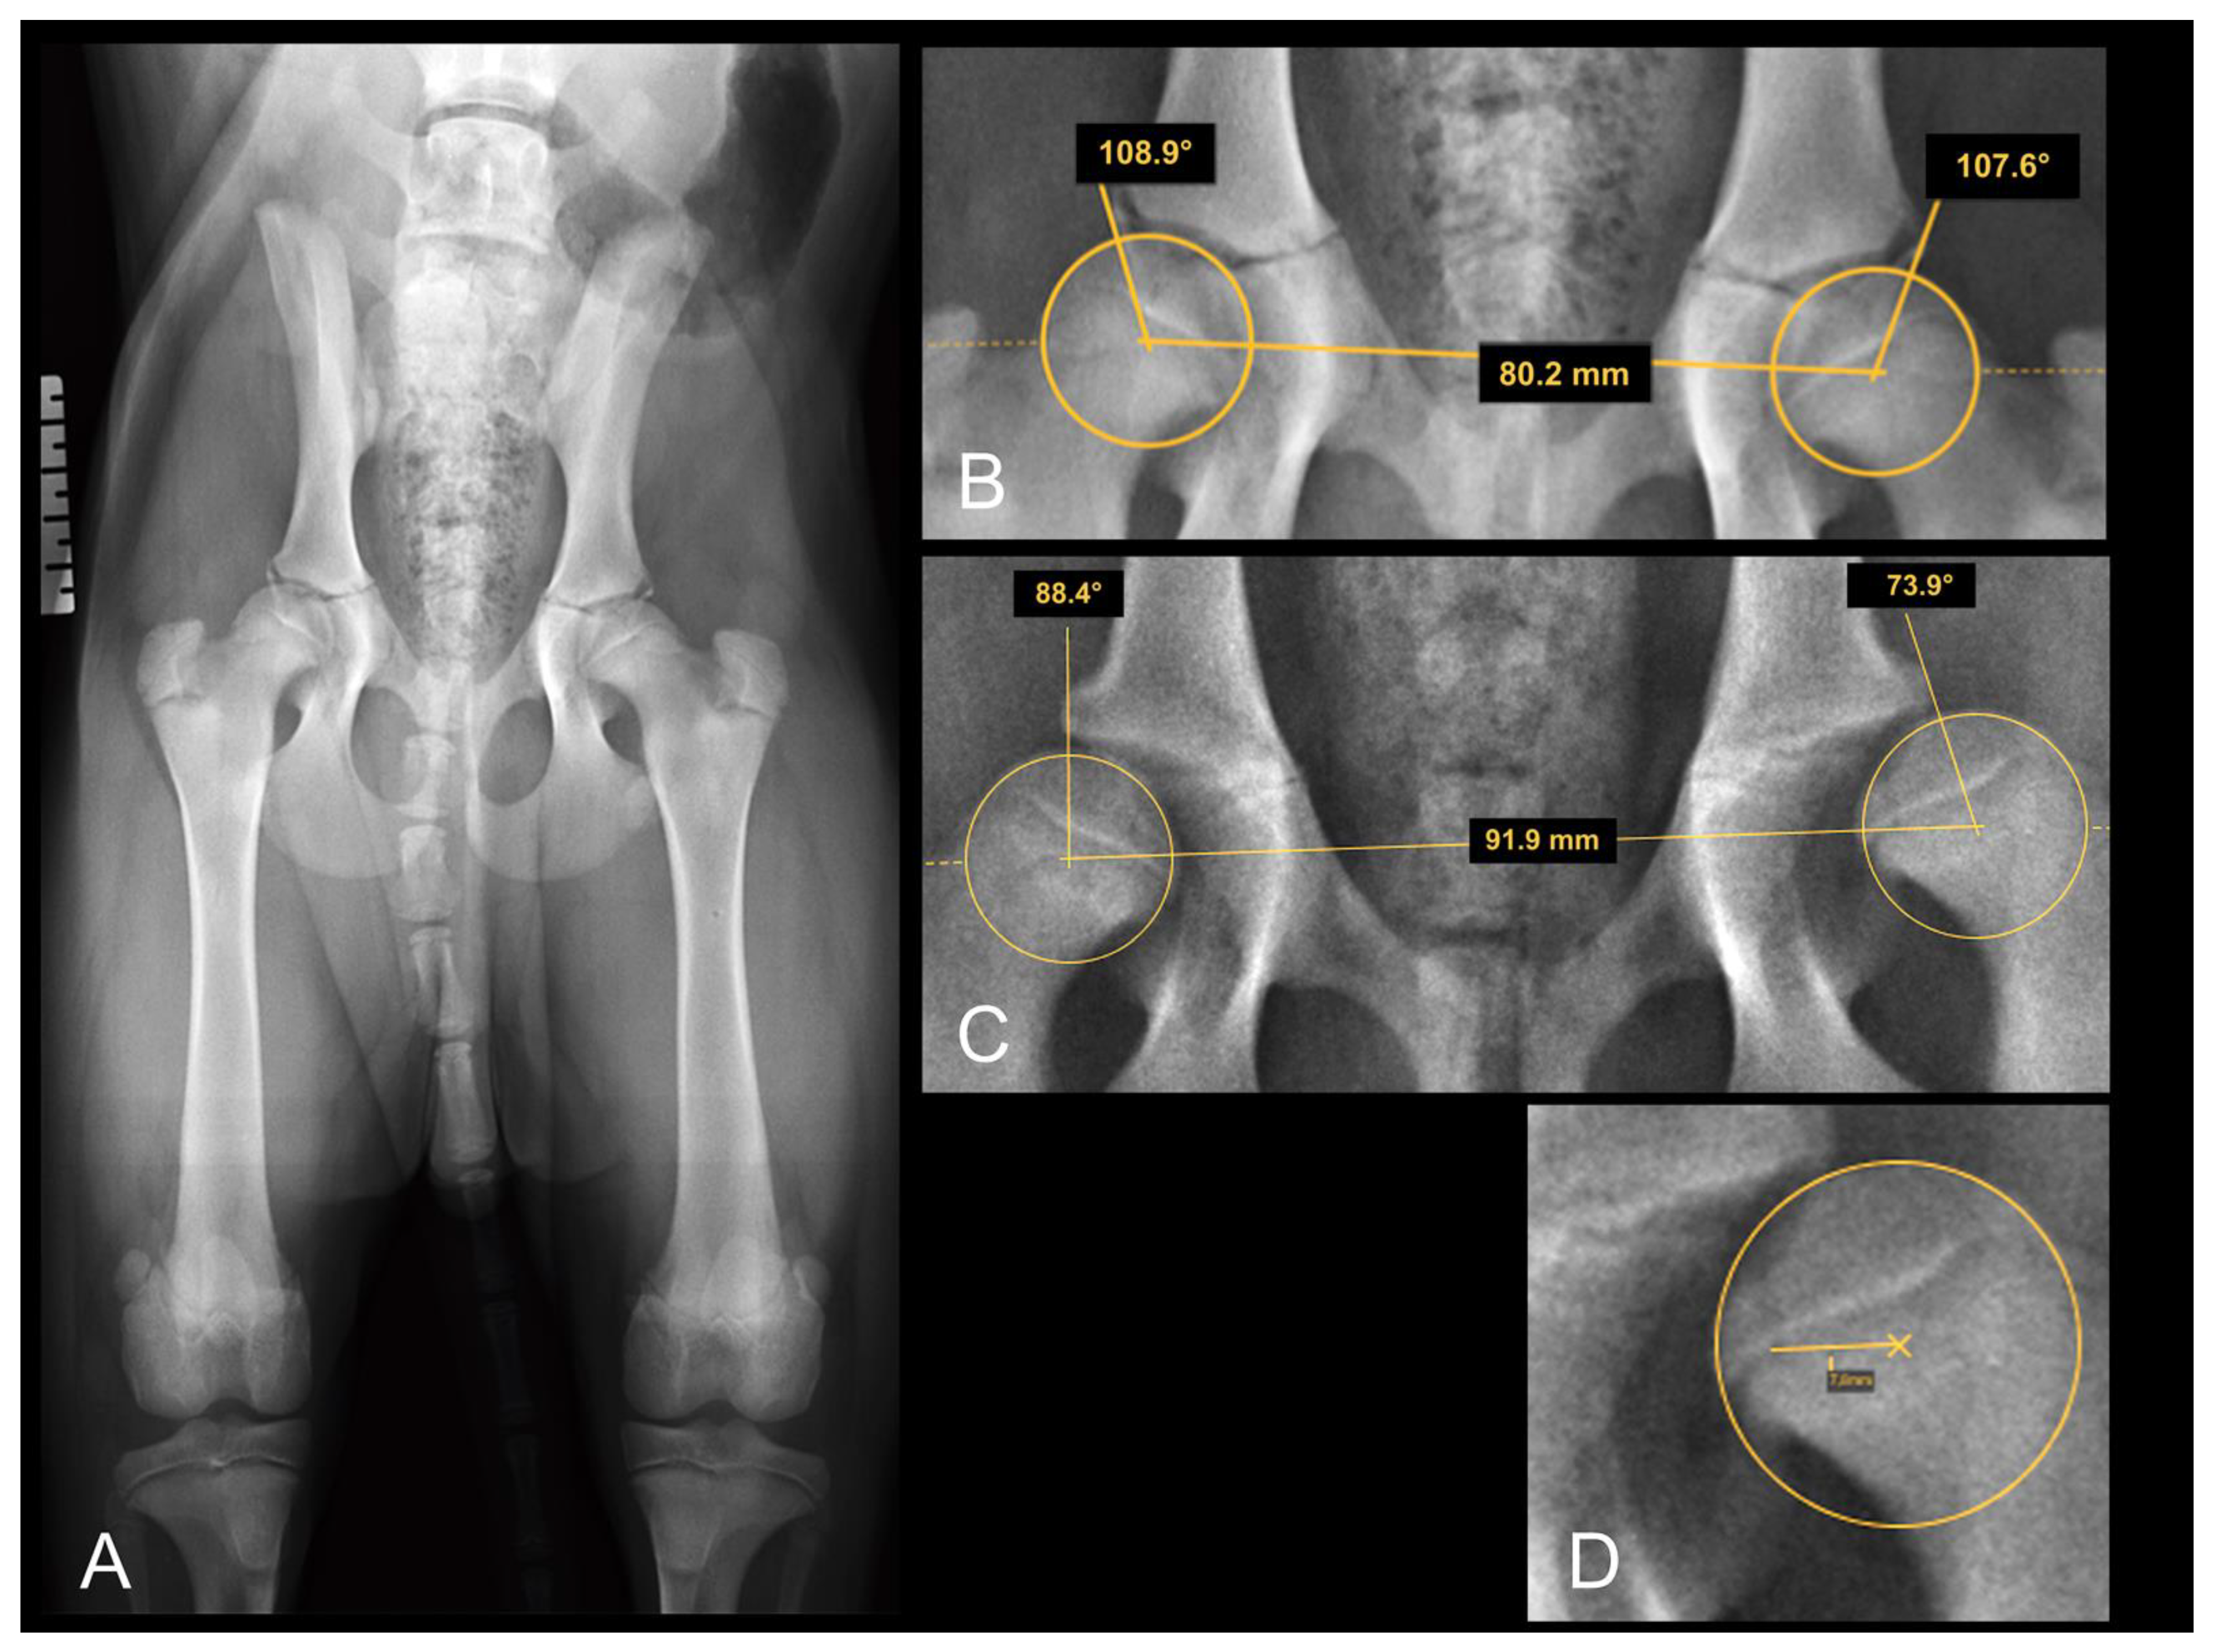

2.5.5. The Distraction Index (DI)

To quantify the DI, ventrodorsal distraction view radiographs (Badertscher method modified by Vezzoni) were taken, and the calculation of the DI was performed using the PennHIP measurement method [26]. The DI is calculated by dividing the distance between the centers of the femoral head and acetabulum by the radius of the femoral head during distraction and is a number between zero (healthy hip) and one (severe laxity). The incidence of hip laxity in dogs with DI ≤ 0.3 and DI ≥ 0.6 is reported to be low and high, respectively [34]. The measurement of the DI on the distraction view radiograph is shown in Figure 2.

2.5.6. Dorsal Acetabular Rim Slope (DARS)

The DARS is the angle between the intersection of the perpendicular line drawn from the center of the femoral head to the mid-sagittal plane of the pelvis/sacrum, and the line drawn tangent to the most lateral point of the dorsal acetabular rim [33]. The DARS is reported to be ≤7.5° in healthy hips, whereas higher values indicate hips with increased laxity [33]. The measurement of the DARS on a DAR-view radiograph is shown in Figure 3A.

2.5.7. The Center Edge Angle (CEA)

The CEA is an angle between the straight line, drawn from the center of the femoral head tangential to the outer edge of the acetabular rim, and the straight line, drawn parallel to the mid-sagittal axis of the pelvis/sacrum on DAR-view radiographs [35,36]. The CEA is used to assess the acetabular coverage of the head of the femur and is reported to be greater than 12° for healthy hips [36]. The magnification of the measurement of the CEA in a Rottweiler dog is shown in Figure 3B.

Figure 2. (A) Distraction view VD radiograph of a four-month-old Rottweiler (same dog as in Figure 1A,B). (B) A magnification of the right and (C) a magnification of the left hip joint demonstrating the distraction index measurements. Note the laxity in the left joint which was not obvious in the extended view.

Figure 3. Dorsal acetabular rim view radiographs of the same Rottweiler shown in Figure 1 A,B as well as Figure 2. Measurement of the dorsal acetabular rim slope is demonstrated on (A) and of the center edge angle on (B). Right is always to the left of the image.